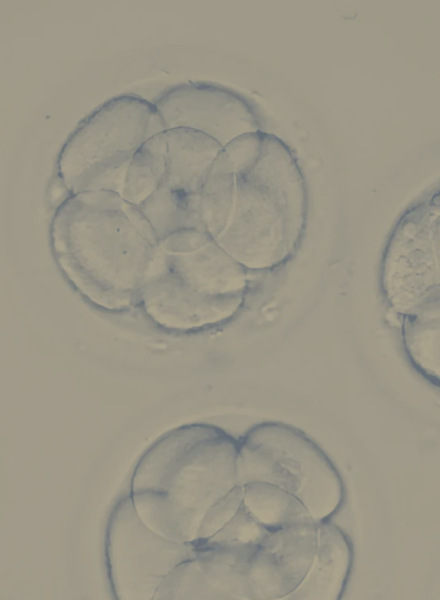

Treat

Receive compassionate, expert-led care throughout your journey, with continuous monitoring and support every step of the way.